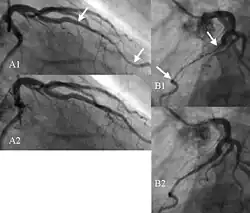

Podstawą rozpoznania jest koronarografia.